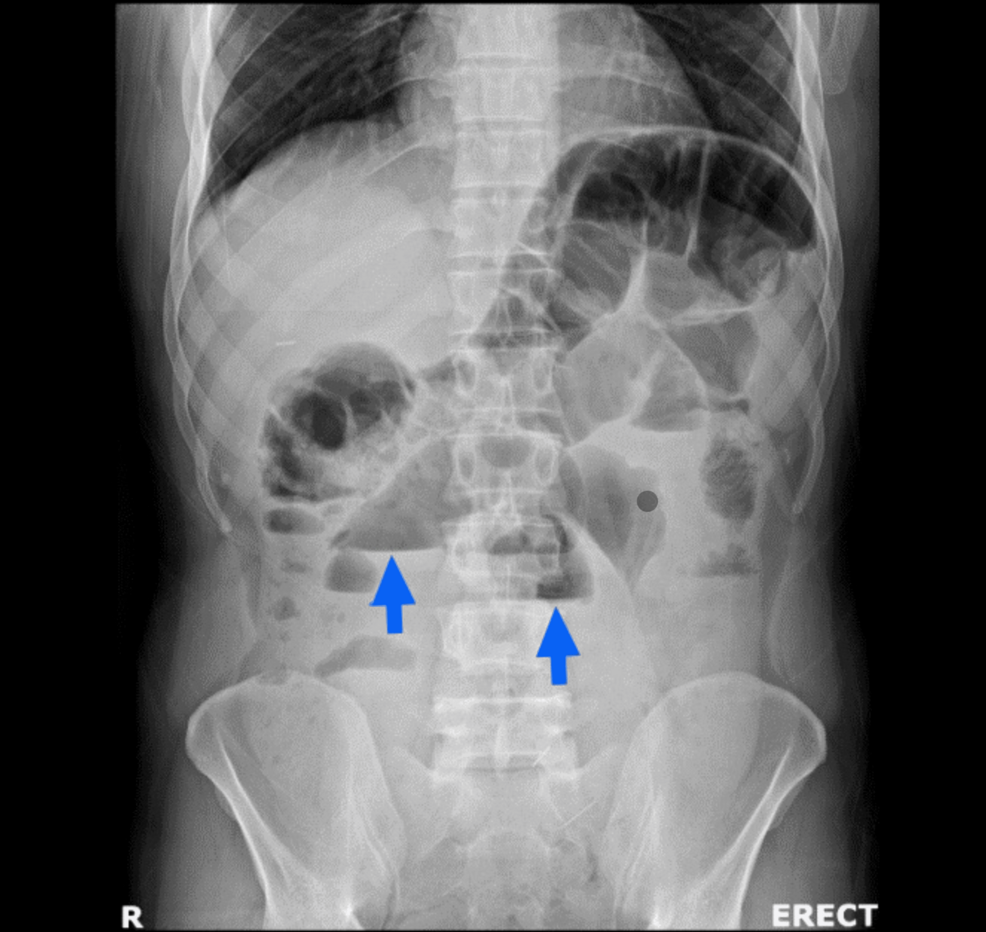

En un caso reciente, una mujer de 66 años se presentó con dolor abdominal intenso y vómitos. Las imágenes de tomografía computarizada revelaron una obstrucción en asa cerrada causada por la apendicitis. Las complicaciones conocidas de la apendicitis incluyen la perforación con peritonitis generalizada, la formación de masas apendiculares, abscesos, sepsis, formación de adherencias y, en raras ocasiones, la obstrucción intestinal.